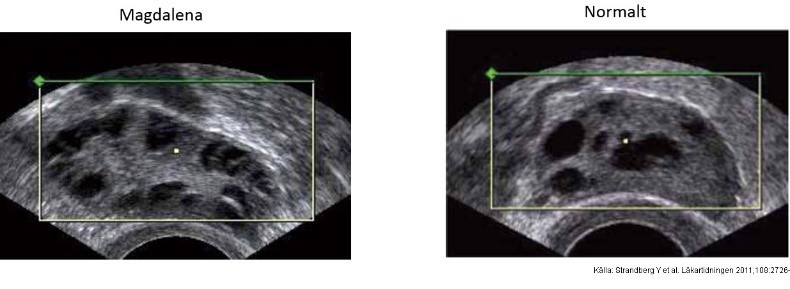

Ung kvinna (18 år) inkommer till vårdcentral. Ej haft menstruationer på 6 mån, gravtest negativt. Ökad behåring på käklinjen samt fått mer acne på slutet. Lätt överviktig. Prover visar normal TSH, LH, FSH, fP-glukos, östradiol och testosteron. Högt insulin, sänkta nivåer av SHBG.

Vilka kriterier för PCOS uppfyller Magdalena?

Magdalena, ej haft menstruation på 6 månader